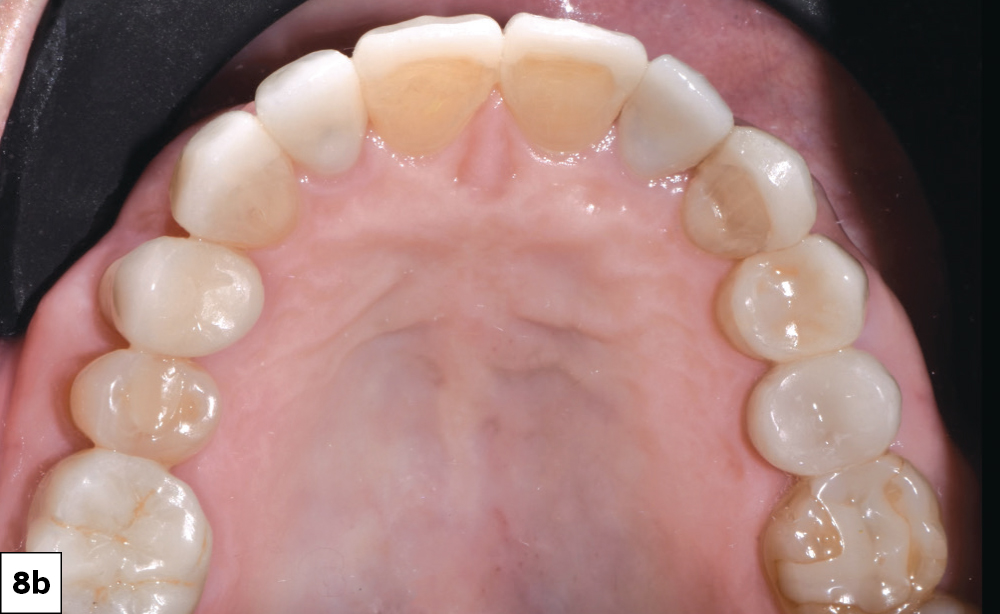

he gingivectomy on #8 & #9 resulted in gingival symmetry

The restorations were seated with Variolink® Esthetic resin cement (Ivoclar Vivadent)

Figures 8a, 8b: The gingivectomy on #8 & #9 resulted in gingival symmetry. The restorations were seated with Variolink® Esthetic resin cement (Ivoclar Vivadent). After tack-curing to facilitate cleanup, I removed excess cement and completed light curing from all aspects to ensure full polymerization. This sequence produced a durable and predictable bond while preserving the customized esthetic characterization of the Obsidian restorations.